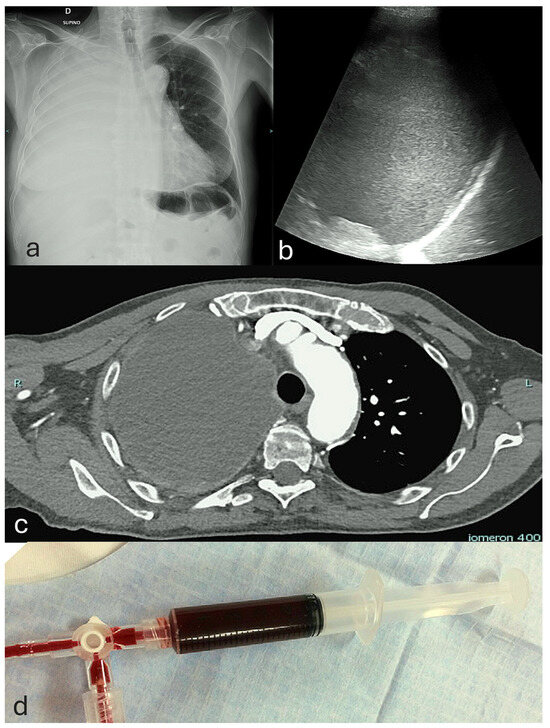

5.1. Overview of Common Complications Associated with Pleural Procedures

5.2. Incidence and Severity of Hemorrhagic Complications in Pleural Interventions

5.3. Procedural Safety Measures and Risk Mitigation for Hemorrhagic Complications in Pleural Interventions